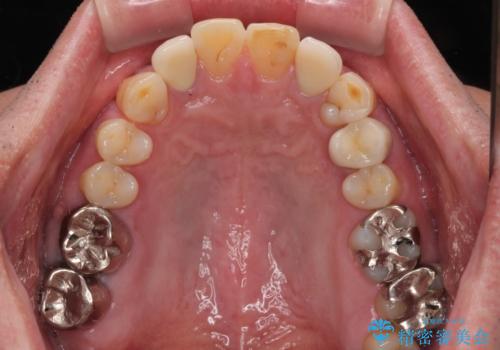

- 前歯の色味が気になるとのことで来院された患者様です。左上の2番目の歯の歯茎のラインと被せものの境目の適合が悪い状態だったのでオールセラミッククラウンによる補綴治療を行っていくことになりました。

金属の土台を外し、ファイバーコアを築造し、オールセラミッククラウンに適切な形に整えました。

左上の2番目の歯の型どりの段階で患者様より右上の2番目の歯も治療をしてほしいとのことで、根管治療(保険診療)、ファイバーコア、オールセラミッククラウンによる補綴治療を行いました。

見た目、機能面共に満足していただけました。

右上2番目の歯の違和感もなくなったと喜んでいただけました。